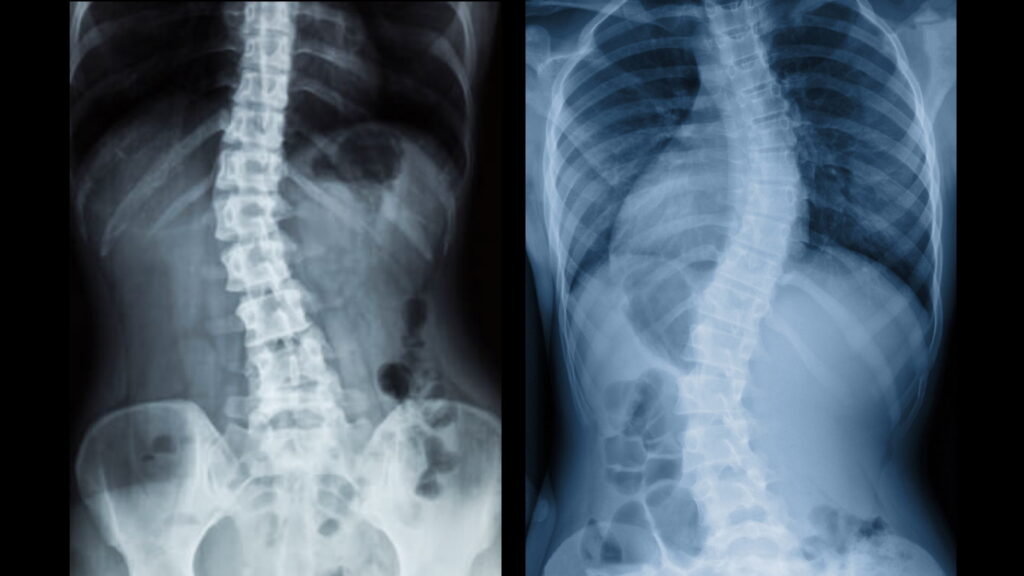

Skolióza je boční zakřivení (vybočení) páteře, na jednu nebo druhou stranu. Zatímco přirozené oblouky páteře (lordotický a kyphotický) pomáhají páteři zvládat „šokové“ stavy – jako otřesy, rány, zvýšenou emoční zátěž nebo nejrůznější krátkodobé vychýlení páteře z různých důvodů, u skoliotického vybočení je to jiné.

Žádné postranní zakřivení páteře není přirozené a jakékoliv boční prohnutí větší než 10 stupňů je diagnostikováno jako skolióza.

Jak už bylo řečeno, vybočení, nebo postranní zakřivení páteře je u každého člověka jiné. Snímek RTG ukazuje na celkem jasné zakřivení do tvaru písmene C. (Pravá strana obrázku je pravá strana těla). Na pravé straně je prohloubení (concave), na levé straně je vychýlení (convex).

Takže pokud se podíváme na ten RTG snímek, pak vidíme, že svaly na pravé straně jsou zkrácené, příliš napjaté. V napětí jsou ale nejen šikmé břišní svaly, vnitřní i vnější, ale taky quadratus lumborum (kvadratický bederní sval) a psoas, hlavní napřimovač a stabilizátor páteře.

Šikmé břišní svaly jsou velmi silné svaly středu těla (core), které táhnou žebra (hrudní koš) a pánev k sobě, jak je vidět na snímku RTG (pravá strana). Můžete vidět, že vzdálenost mezi posledním dolním žebrem a vrchní hranou pánevní kosti je kratší na pravé straně než na levé. Můžete taky vidět, že bok na pravé straně směřuje víc nahoru než na levé straně, protože kontrahované svaly táhnout kyčel nahoru k hrudnímu koši. To znamená, že bude taky nerovnováha mezi pravou a levou nohou.